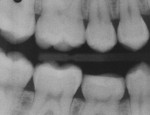

A 13-year-old girl had a retained ankylosed mandibular right primary second molar (Figure 1). The tooth had occlusal caries. In addition, a bitewing radiograph and lateral transillumination revealed a substantial caries lesion on the mesial surface (Figure 2). A panograph from a year prior (not pictured) showed congenital absence of the second premolar.